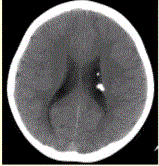

问题 患者男,20岁,面部皮脂腺瘤,头CT显示如下图。 有关该病的描述正确的是

选项 A.室管膜下结节无钙化 B.70%伴有室管膜下巨细胞星形细胞瘤 C.结节强化提示病变恶变 D.影像学首选MRI E.50%为遗传性,常染色体显性遗传

答案 E